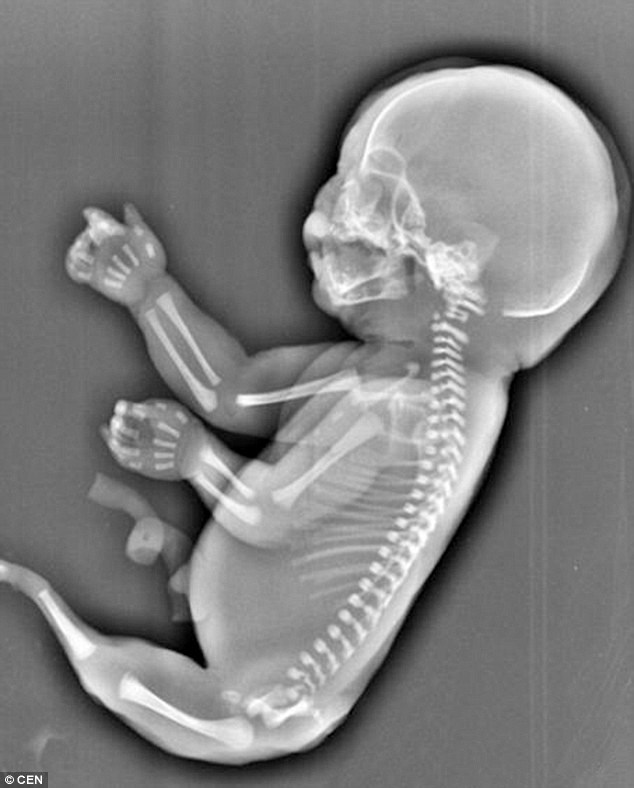

Bà mẹ trẻ đau lòng khi thấy hình ảnh về thai nhi. (Nguồn: CEN)

Theo đó, thai nhi sáu tháng tuổi trên không có hai chân và lại "mọc đuôi" giống như người cá.

Các bác sỹ cũng cho biết, thai nhi trên cũng không có bàng quang và hai lá gan phát triển không đồng đều.

Theo các bác sỹ, thai nhi trên đã mắc phải hội chứng người cá, hay có tên khoa học là "Hội chứng Mermaid". Hội chứng này gây ra dị tật bẩm sinh hiếm gặp khi hai chân hợp nhất với nhau.

Nguyên nhân gây ra hội chứng Mermaid vẫn là một bí ẩn đối với y học thế giới. Tỷ lệ thai nhi mắc hội chứng này là 1/100.000./.